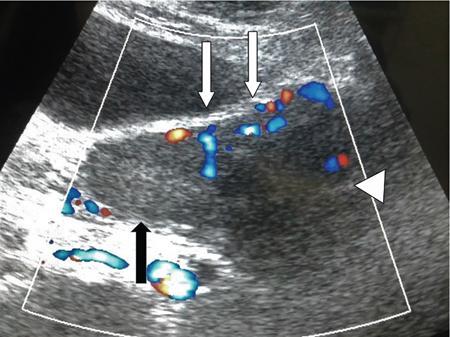

Venkatraman Indiran Bridging vessel sign Multiple vascular channels (white arrows) connecting uterus (black arrow) to an adjacent pelvic mass on imaging studies, is known as the ‘bridging vessel’ or ‘bridging vascular’ sign. Originally described on colour Doppler imaging, but also seen on computed tomography (CT) or magnetic resonance imaging (MRI). Helps in differentiating a mass of uterine origin, typically a subserosal fibroid, from other pelvic masses. Sensitivity and specificity of ‘bridging vessel sign’ in identifying subserosal fibroids range from 90% to 100%. (Best seen when subserosal fibroid is larger than 3 cm in diameter.) Ovarian masses invading the uterus may rarely produce a falsely positive bridging vessel sign. Broccoli sign Submucosal uterine leiomyoma prolapsing into the endocervical canal, along with its stalk in the uterine cavity on sagittal T2-weighted images together is called as ‘broccoli sign’ (white arrow). Submucosal uterine leiomyoma Bunch of grapes Intrauterine mass with cystic spaces without any associated foetal parts on ultrasound (white arrows) classically gives a ‘snow storm’ or ‘bunch of grapes’ appearance. Complete hydatidiform mole Hourglass sign Deep infiltrating endometriosis (DIE) affecting the posterior urinary bladder wall, usually in the midline, causes loss of its distensibility, resulting an hourglass configuration of urinary bladder. Deep infiltrating endometriosis (DIE) Hyperechoic line sign Normal endometrium surrounding the endometrial polyp on ultrasound appear as a hyperechoic rim on transvaginal ultrasound is called as ‘hyperechoic line sign’. Hyperechoic line sign represents a focal intracavitary lesion. Endometrial polyp Indian head dress sign/moose antler sign In deep infiltrating endometriosis (DIE), adhesions between the anterior wall of rectosigmoid and posterior wall of uterus, stretches the muscular layer of the bowel and creates an infiltrative nodule with parallel lines that extend from the adhesion to the rectosigmoid. This is called as ‘Indian head dress sign/moose antler sign’ (white arrow). This is seen on sagittal T2-weighted images as well as transvaginal ultrasound. Deep infiltrating endometriosis (DIE) Interstitial line sign An echogenic line that extends into the upper regions of the uterine horn and borders the margin of the intramural gestational sac is called as the ‘interstitial line sign’ (white arrow). Seen best on transabdominal/transvaginal ultrasound. Specific finding of interstitial pregnancy Mushroom cap sign Mushroom-shaped lesion which is seen displaced into the bowel lumen in patients with solid invasive endometriosis of the rectosigmoid colon on axial or sagittal T2-weighted MRI is called as ‘mushroom cap sign’ (red box and white arrow). Low signal intensity base of the mushroom corresponds to hypertrophy and fibrosis of the muscularis propria, whereas the high intensity cap represents oedematous mucosa and submucosa. Deep infiltrating endometriosis (DIE) Pedicle artery sign Feeding vessel sign Central vessel entering the endometrium from the surrounding myometrium colour Doppler imaging of the endometrium in endometrial polyps is called as pedicle artery sign (white arrow). Endometrial polyps in women with postmenopausal bleeding. (Sensitivity of 76.5%; specificity of 95.3%.) Popcorn ball calcification Dense, amorphous calcifications of uterine fibroids seen on the plain radiographs is called as ‘popcorn calcification’ (white arrow). Confluent, coarse calcification constitutes the most specific radiographic sign of a benign uterine fibroid; but only 10% or fewer of fibroids show calcification. Question mark sign of uterus The uterine corpus that is flexed backward with the fundus of the uterus facing the posterior pelvic compartment and the cervix directed anteriorly toward the urinary bladder, is called as question mark sign of uterus (white arrow). Also called as comma-shaped uterus. 93% specificity and 75% sensitivity in diagnosing adenomyosis uterus. Sliding organs’ sign When the uterus and ovaries glide freely over the posterior and anterior organs (such as rectum and urinary bladder, respectively) during real-time dynamic transvaginal sonography, it is called as ‘positive sliding organs’ sign’. In case of adhesions due to endometriosis, free gliding of organs is absent and is called as negative sliding sign. Snowstorm sign Grainy appearance with low-level homogeneous internal echoes which move slowly downward due to their viscosity seen in endometrioma on transvaginal ultrasound is called as snowstorm sign. Endometriomas Split fibre sign Presence of curvilinear T2 hypointense strands within the degenerated leiomyoma separated by the fluid accumulation and oedema is called as the ‘split fibre’ sign. Split fibre sign on T2-weighted MRI can be used to differentiate hydropic degeneration from other conditions like malignant change. Three-line sign or triple line sign or trilaminar appearance Shortly before ovulation, two additional bright linear echoes outline two hypoechoic layers of endometrium with a central hyperechoic line in the endometrium (white arrow). It is called as the ‘three-line sign’ or ‘triple line sign’ or trilaminar appearance. A triple-line pattern with a moderate endometrial thickness is associated with a good clinical outcome on in-vitro fertilization. Venetian blind shadowing Also known as ‘rain shower’ appearance Heterogeneous myometrial appearance due to hyperechoic heterotopic endometrial tissue and hypoechoic hyperplastic smooth muscle appearing as vertical linear bands of shadows on ultrasound is called as ‘Venetian blind shadowing’. Classically described in uterine adenomyosis; sometimes in uterine fibroids also. Bead on strings sign Thickened endosalpingeal longitudinal folds within a dilated fallopian tube without wall thickening appears as small mural nodules on cross-sectional images on ultrasound is called as ‘bead on strings’ appearance. Seen in chronic salpingitis Beaded tube Multiple constrictions along the course of fallopian tube may form due to scarring is seen in genitourinary tuberculosis and shows a ‘beaded’ appearance. Female genital tuberculosis Cogwheel sign Thickened endosalpingeal longitudinal folds within a dilated fallopian tube with thickened wall appears as small mural nodules on cross-sectional images across the long axis of the fallopian tube on ultrasound (white arrows) produce a characteristic ‘cogwheel’ appearance. Seen in acute salpingitis. The presence of thickened longitudinal folds is pathognomonic for hydrosalpinx. Cobblestone tube Rounded filling defects in cases of fallopian tube tuberculosis are called as the cobblestone pattern. Is an effective radiographic sign of intraluminal scarring and adhesions. Female genital tuberculosis Golf club tube Occlusion of the isthmus or fimbrial end of the fallopian tube and filling up of the tube with serous or clear fluid produces a moderate dilatation at the fimbrial end, produces a ‘golf club–like appearance’. Female genital tuberculosis Halo sign Thin radiolucency seen separating the loculated peritubal collection from the dilated tube, is known as the ‘halo sign’. This radiolucent halo represents the thickened wall of the tube. Female genital tuberculosis Incomplete septation sign Thin linear structures appearing to protrude into the tubular cystic adnexal structures, but not touching the opposite walls is called ‘incomplete septation sign’ of hydrosalpinx. Apparent septae are due to apposition of the inner walls of the dilated and folded fallopian tube. Hydrosalpinx Pipe stem tube Rigid contour of the fallopian tube seen in cases of fallopian tube tuberculosis is called as ‘pipe stem appearance’. Female genital tuberculosis Leash sign Typical eccentric leash of vessels on colour Doppler (white arrow) showing a low resistance placental type of flow on spectral Doppler in fallopian tube ectopic pregnancies is called as leash sign.